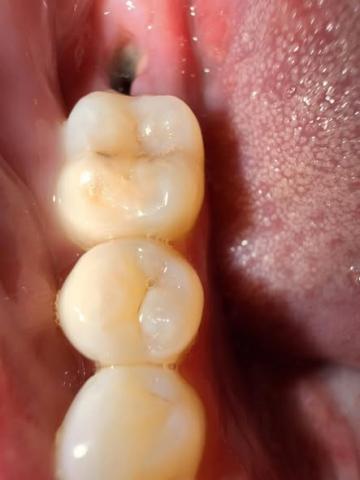

I see a dark, fairly deep socket behind the last visible molar (the extraction site).

No obvious pus or large swelling visible in the photo and you report no pain — both reassuring.

Surrounding teeth look intact. Photo lighting/angle limits how much I can see (I can’t check bleeding under the gum or feel for mobility).

Bottom line: this looks like a normal 7-day post-extraction socket (deep appearance from the clot/early granulation tissue) rather than an acute complication — but a picture can’t replace a clinical exam.